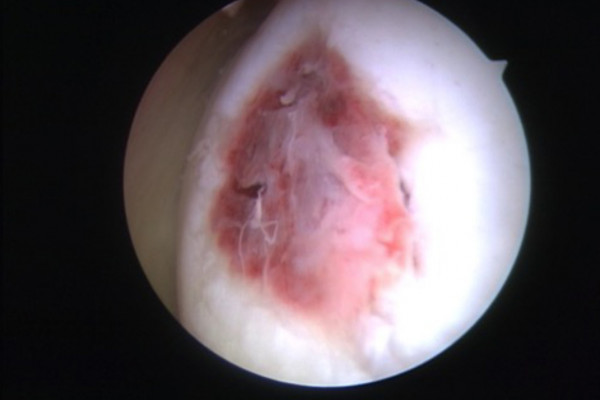

Ergebnis 6 Wochen nach Mikrofrakturierung

Das aus dem Knochenmark austretende Blut ist reich an Stammzellen (Zellen die die Fähigkeit besitzen sich je nach Bedarf in unterschiedliche, spezialisierte Gewebezellen zu verwandeln) und füllt den Defekt zunächst mit einem Blutklumpen (Koagel) auf. Durch den Kontakt mit der Gelenkflüssigkeit und die im Gelenk herrschenden Scher- und Druckbelastungen wandelt sich dieses Blutkoagel in Ersatzknorpel (Faserknorpel) um und füllt den Defekt so auf. Dieser Eingriff erfolgt minimalinvasiv im Rahmen einer Gelenkspiegelung. Zum Schutz des sich neu bildenden Knorpels ist eine Entlastung für 6 Wochen mit einer anschließenden langsamen Belastungssteigerung erforderlich.